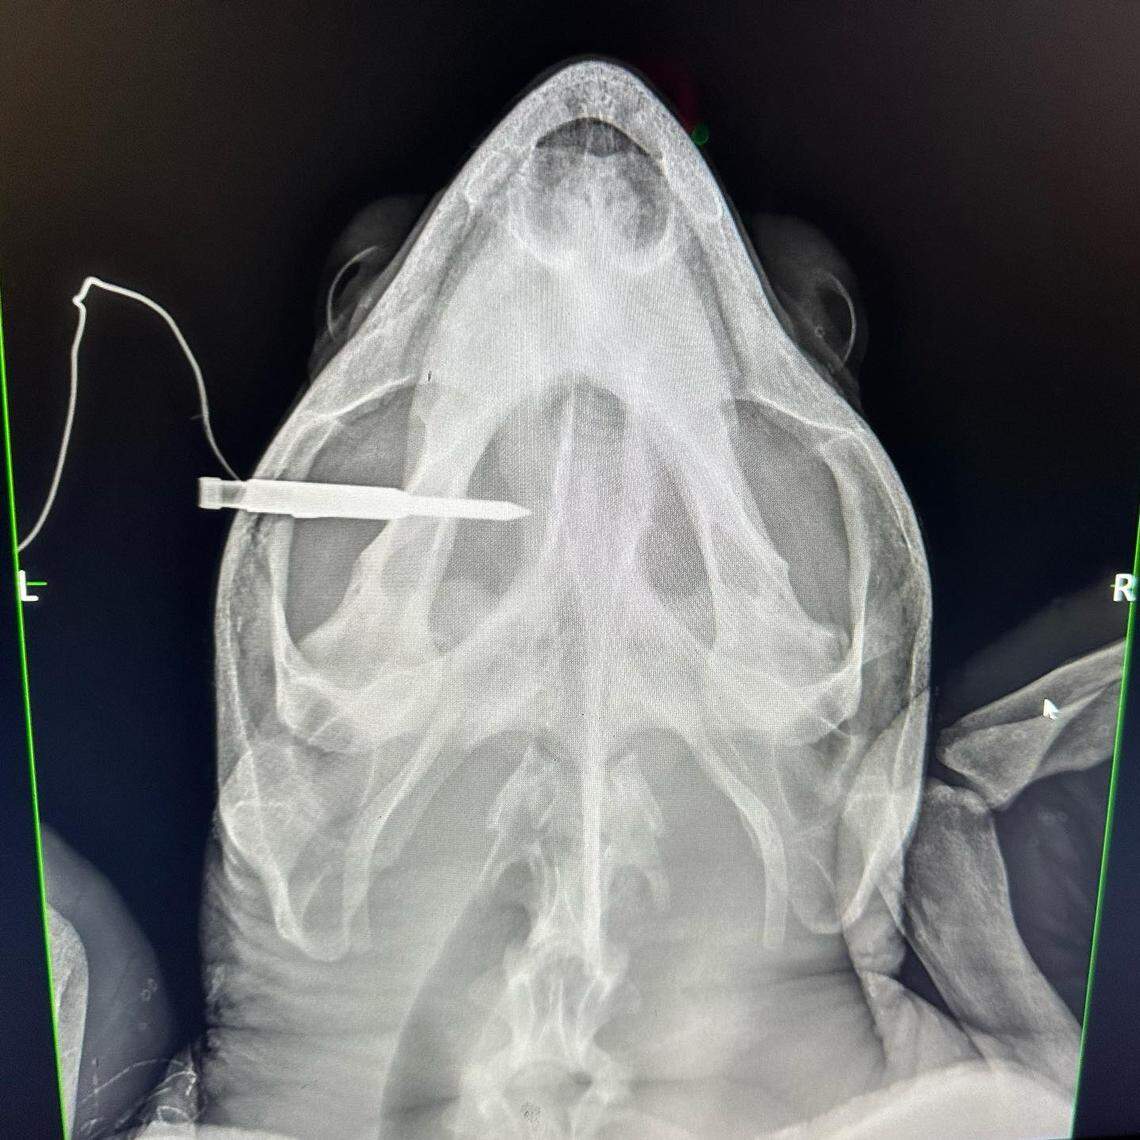

An X-ray image shows a fishing spear lodged in the head of a loggerhead sea turtle. The animal was euthanized at the Turtle Hospital in the Florida Keys Saturday, Oct. 19, 2023.

An X-ray image shows a fishing spear lodged in the head of a loggerhead sea turtle. The animal was euthanized at the Turtle Hospital in the Florida Keys Saturday, Oct. 19, 2023. The Turtle Hospital

The Turtle Hospital in Marathon began caring for the turtle, which workers named Aubie (for Auburn University), last Thursday when a guest at a Long Key resort found him in distress. A steel spear was sticking out of his head and one of his front flippers was entangled in fishing line.

But by Saturday, he was showing signs of neurological damage. A CT scan showed the spear pierced completely through his skull and into his brain casing, “causing irreparable damage,” Zirkelbach said.